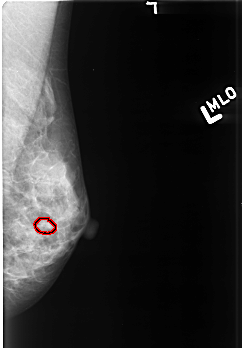

B_3418_1.LEFT_MLO

LEFT_MLO LINES 4176 PIXELS_PER_LINE 2904 BITS_PER_PIXEL 12 RESOLUTION 50 OVERLAY

FILE: B_3418_1.LEFT_MLO.OVERLAY

TOTAL_ABNORMALITIES 1

ABNORMALITY 1

LESION_TYPE CALCIFICATION TYPE PUNCTATE-AMORPHOUS DISTRIBUTION CLUSTERED

ASSESSMENT 4

SUBTLETY 3

PATHOLOGY BENIGN

TOTAL_OUTLINES 1

BOUNDARY